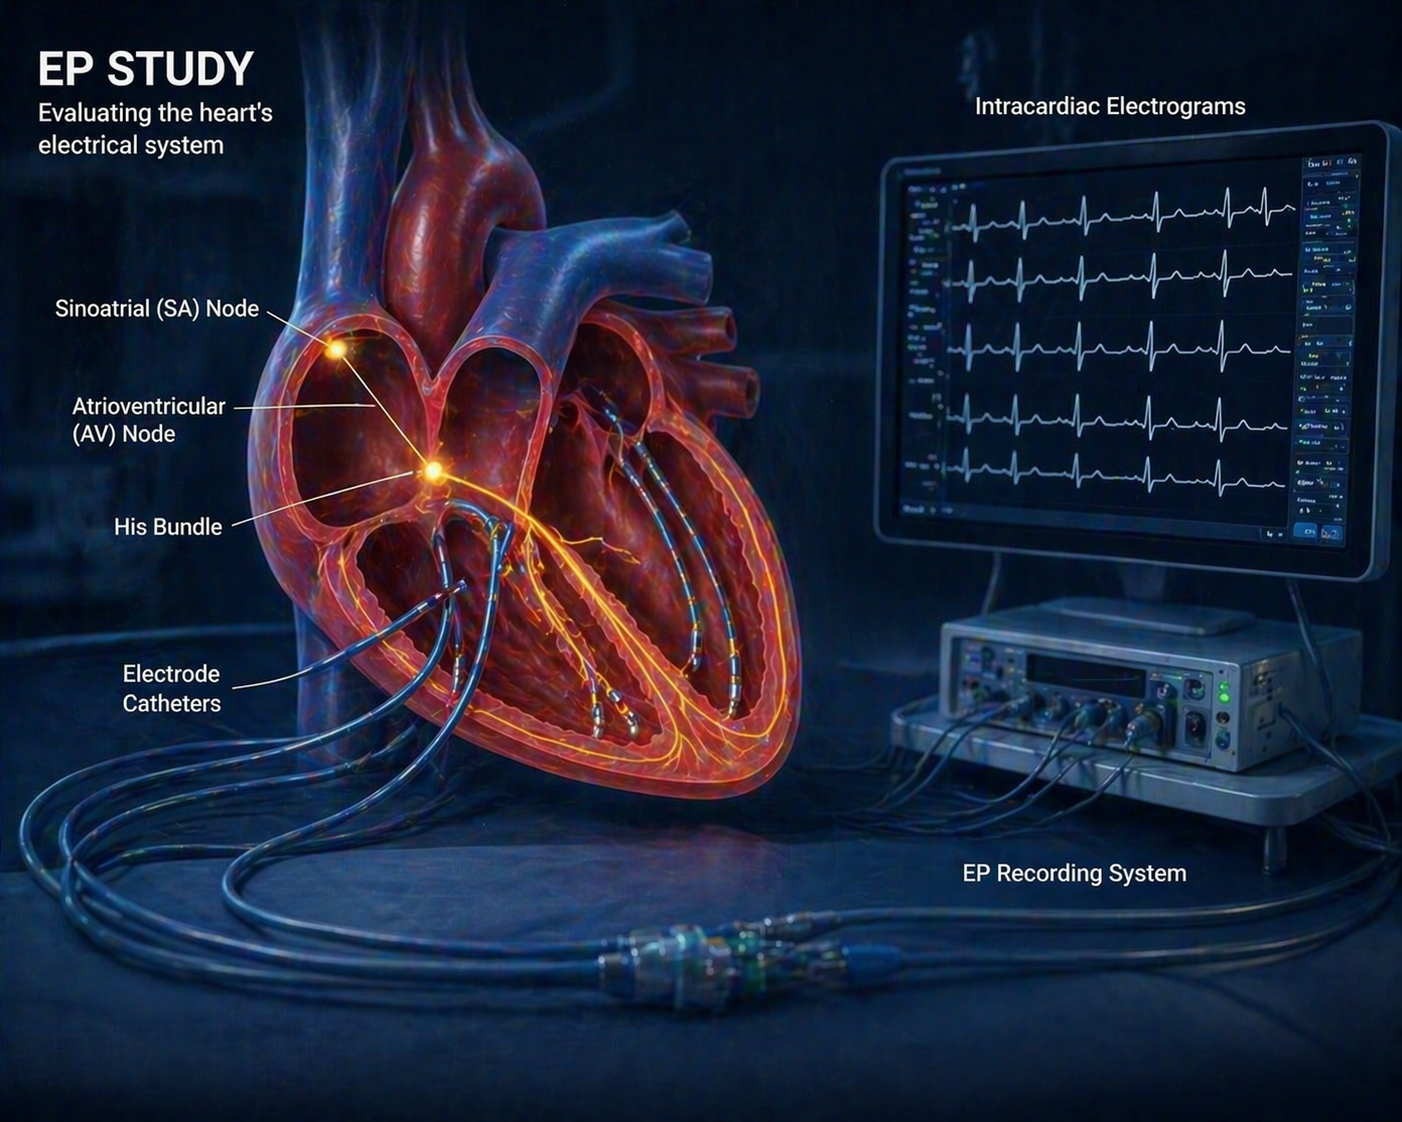

Minimally invasive RF ablation to treat abnormal rhythms with precision and monitoring for better outcomes.

Comprehensive electrophysiology study to diagnose rhythm disorders with precision and monitoring for better outcomes.